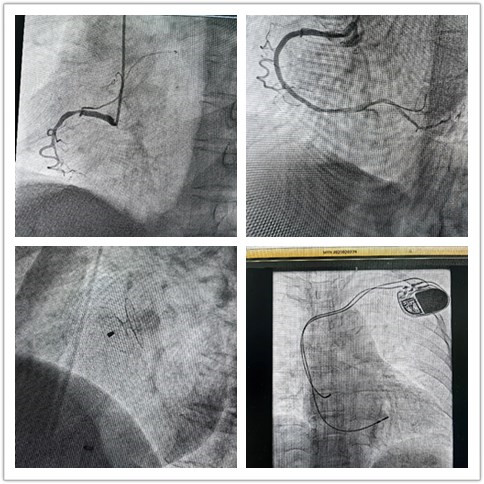

“组团式”帮扶队员—心内科邓纪钊,立即组织指导多学科团队开通胸痛绿色通道,有条不紊进行急诊术前相关检查,诊断为急性下壁心肌梗死。绕行病房,直达介入手术室,仅用32分钟顺利开通血管,患者转危为安,预后良好。

用“心”医治,点亮生命,是医者的初心使命。借力“组团式”帮扶,镇安县医院心内科救治能力和水平不断提高,业务范围不断扩展,先后完成多例卵圆孔未闭封堵、永久性心脏起搏器植入、心律失常射频消融术等。县医院从2022年3月组建介入科至今,截至发稿,冠脉介入手术已逾1000例,急诊冠脉内介入治疗手术已过百例,无1例手术相关医疗事件发生。这是镇安县医院发展史上的里程碑,也是前行的新起点。相信在五楼自拍